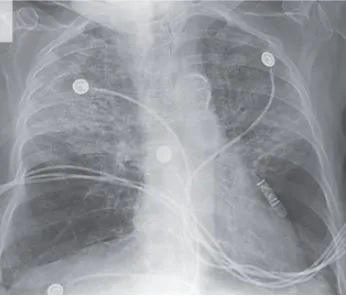

IRA + Icterícia: Um Caso que Exige Investigação Detalhada

IRA + Icterícia: Um Caso que Exige Investigação Detalhada